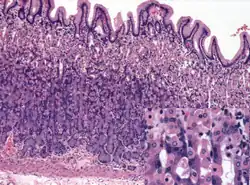

Wall

Like the other parts of the gastrointestinal wall, the human stomach wall from inner to outer, consists of a mucosa, submucosa, muscular layer, subserosa and serosa.[19]

The inner part of the stomach wall is the gastric mucosa a mucous membrane that forms the lining of the stomach. The membrane consists of an outer layer of columnar epithelium, a lamina propria, and a thin layer of smooth muscle called the muscularis mucosa. Beneath the mucosa lies the submucosa, consisting of fibrous connective tissue.[20] Meissner's plexus is in this layer interior to the oblique muscle layer.[21]

Outside of the submucosa lies the muscular layer. It consists of three layers of muscular fibres, with fibres lying at angles to each other. These are the inner oblique, middle circular, and outer longitudinal layers.[22] The presence of the inner oblique layer is distinct from other parts of the gastrointestinal tract, which do not possess this layer.[23] The stomach contains the thickest muscular layer consisting of three layers, thus maximum peristalsis occurs here.

Glands

The mucosa lining the stomach is lined with gastric pits, which receive gastric juice, secreted by between 2 and 7 gastric glands. Gastric juice is an acidic fluid containing hydrochloric acid and digestive enzymes.[24] The glands contains a number of cells, with the function of the glands changing depending on their position within the stomach.

Within the body and fundus of the stomach lie the fundic glands. In general, these glands are lined by column-shaped cells that secrete a protective layer of mucus and bicarbonate. Additional cells present include parietal cells that secrete hydrochloric acid and intrinsic factor, chief cells that secrete pepsinogen (this is a precursor to pepsin- the highly acidic environment converts the pepsinogen to pepsin), and neuroendocrine cells that secrete serotonin.[25]

Glands differ where the stomach meets the esophagus and near the pylorus.[26] Near the gastroesophageal junction lie cardiac glands, which primarily secrete mucus.[25] They are fewer in number than the other gastric glands and are more shallowly positioned in the mucosa. There are two kinds - either simple tubular glands with short ducts or compound racemose resembling the duodenal Brunner's glands. Near the pylorus lie pyloric glands located in the antrum of the pylorus. They secrete mucus, as well as gastrin produced by their G cells.[27]